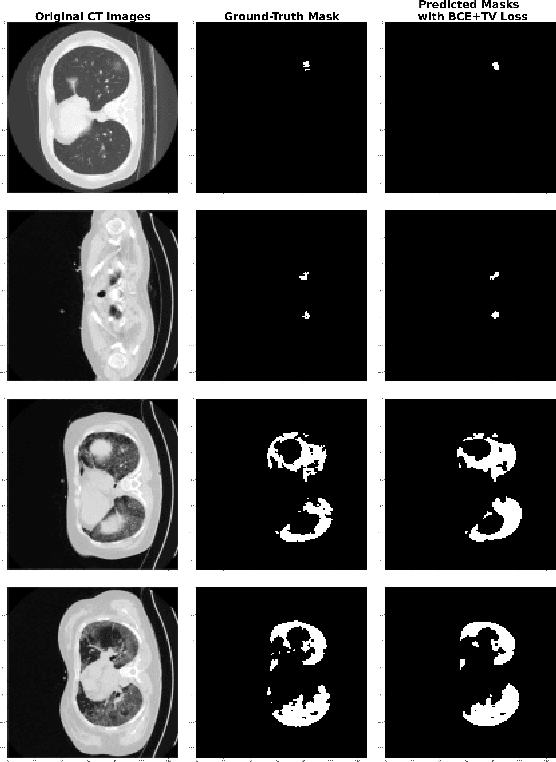

Abstract:The novel corona-virus disease (COVID-19) pandemic has caused a major outbreak in more than 200 countries around the world, leading to a severe impact on the health and life of many people globally. As of mid-July 2020, more than 12 million people were infected, and more than 570,000 death were reported. Computed Tomography (CT) images can be used as an alternative to the time-consuming RT-PCR test, to detect COVID-19. In this work we propose a segmentation framework to detect chest regions in CT images, which are infected by COVID-19. We use an architecture similar to U-Net model, and train it to detect ground glass regions, on pixel level. As the infected regions tend to form a connected component (rather than randomly distributed pixels), we add a suitable regularization term to the loss function, to promote connectivity of the segmentation map for COVID-19 pixels. 2D-anisotropic total-variation is used for this purpose, and therefore the proposed model is called "TV-UNet". Through experimental results on a relatively large-scale CT segmentation dataset of around 900 images, we show that adding this new regularization term leads to 2\% gain on overall segmentation performance compared to the U-Net model. Our experimental analysis, ranging from visual evaluation of the predicted segmentation results to quantitative assessment of segmentation performance (precision, recall, Dice score, and mIoU) demonstrated great ability to identify COVID-19 associated regions of the lungs, achieving a mIoU rate of over 99\%, and a Dice score of around 86\%.